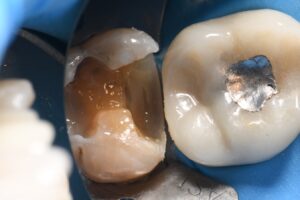

March 10, 2026 (Afternoon tea pics 2341.3: Kerr Simplishade | Rhondium DME | Garrison Dental Solutions – North America) Getting d o w n with DME. #RhondiumDME #KerrSimplishade #GarrisonCompositight Previous Post